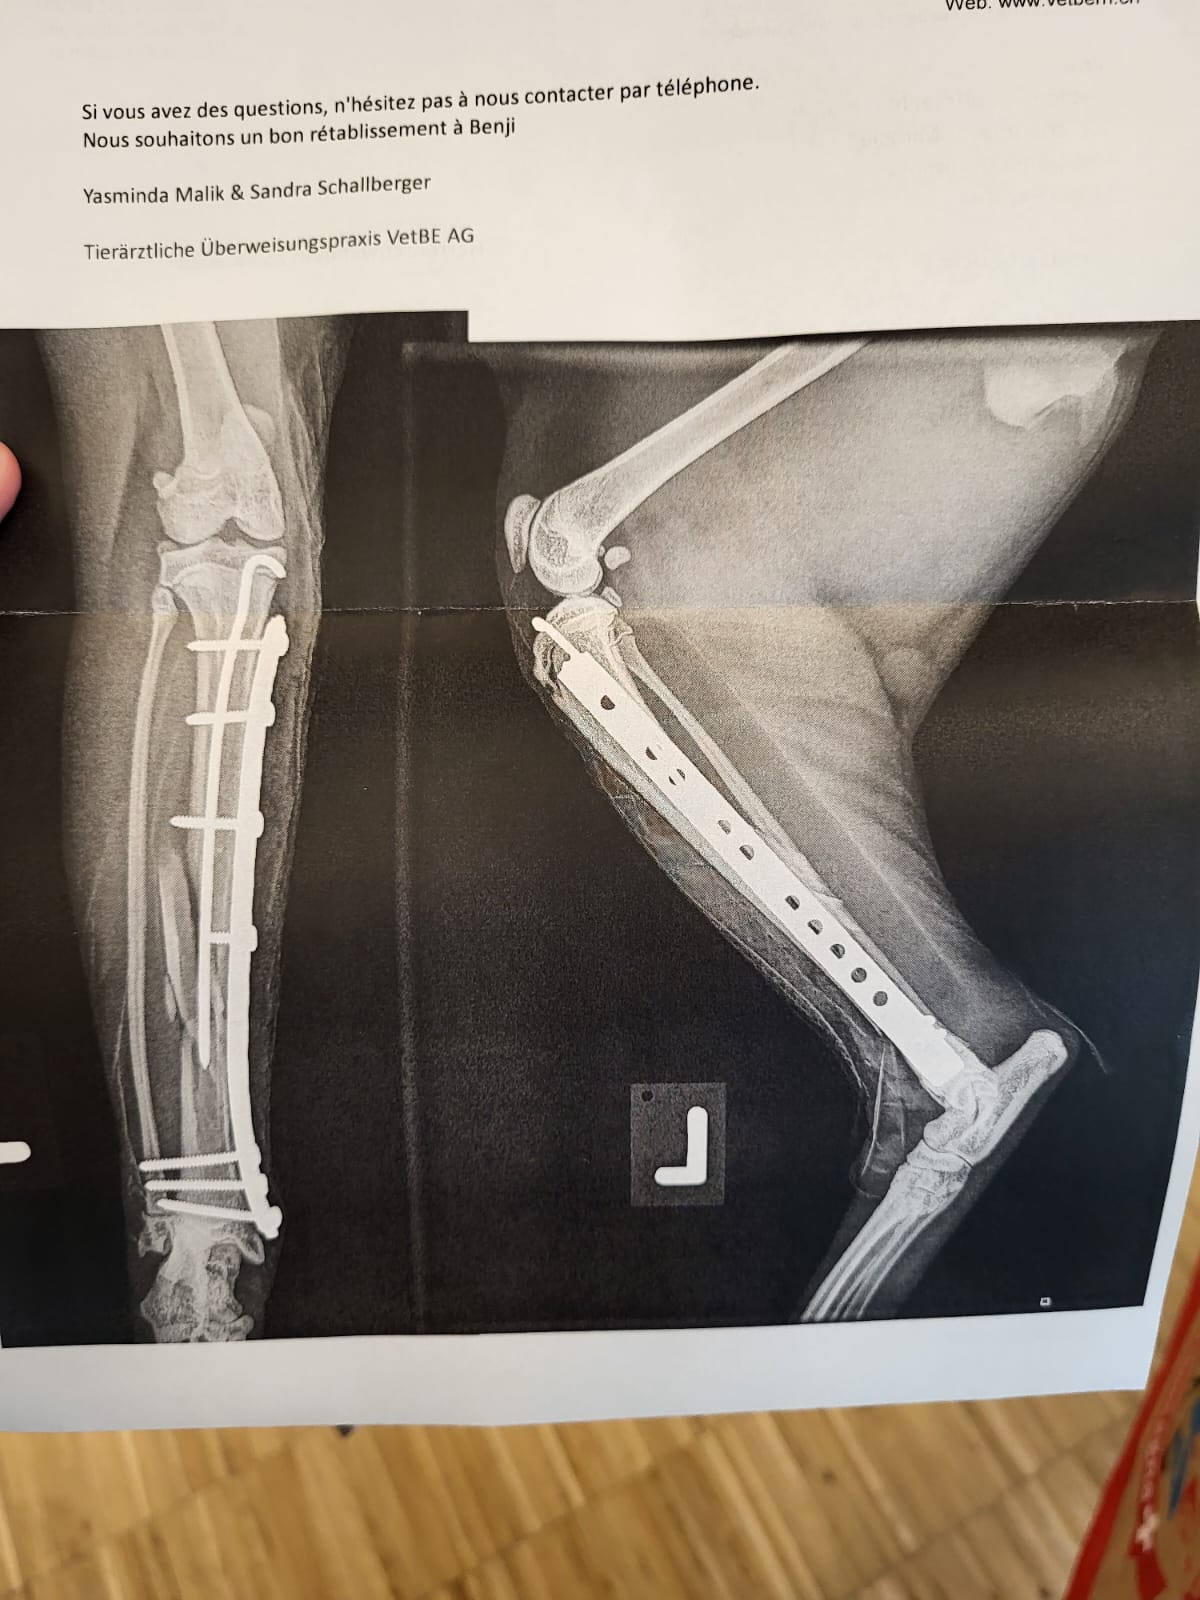

Puis Benji est arrivé également percuté par une voiture, lui a du être opéré d'une vilaine fracture du tibias.

Céleste à été opérer de la mâchoire et Benji lui a du se faire poser un broche et une plaque à une patte.

Céleste et Benji ont du être opéré après avoir été percuté par des voitures. Céleste à été opérer de la mâchoire et Benji lui a du se faire poser un broche et une plaque à une patte.